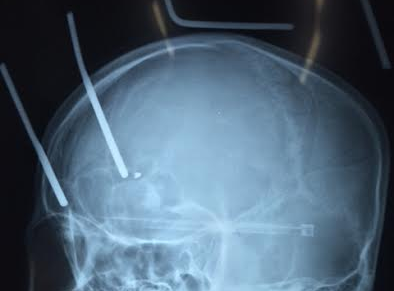

Hai chiếc đinh của chiếc cào sắt đâm xuyên 9 cm từ đỉnh đầu vào não anh Tú (Hà Tĩnh). Rất may sau đó, người này được các bác sĩ phẫu thuật cứu sống.